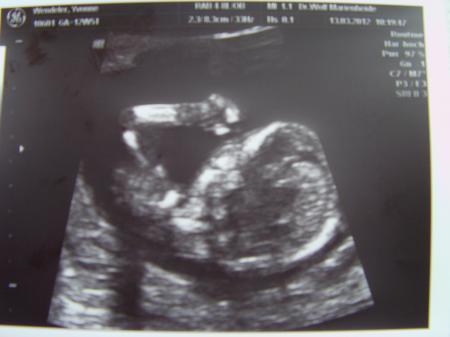

Brandneue Fotos vom heutigen FA Termin :) Das Baby misst ca. 7,2 cm und es geht "Ihm" bestens! Hat sich viel bewegt und man konnte die Fingerchen schon wunderbar erkennen und auch einzelne Gesichtspartien :) Als er mit doppler das Herz ansehen wollte,schmunzelte mein FA und sagte :"Na,bleibst Du wohl liegen!?" :D War nicht ganz so einfach für Ihn das festzuhalten ;) Was das outing angeht wollte er sich nicht dazu äussern.Zitat:" Vor der 16 SSW. sage ich garnichts...das ist mir zu ungenau!" Naja,schade,aber mit so einer Aussage hab ich fast gerechnet.Aber auch ich konnte nichts erkennen...weder das eine noch das andere ;) Der nächste Termin wäre am 24.04. ...ob ich das so lange aushalte ohne Baby TV!? Die Bildchen möchte ich euch nicht vorenthalten ;)

Bild zu FA Termin - Forum für September - Mamis

Meiiii wie süüüüß, ein Daumenlutschfoto